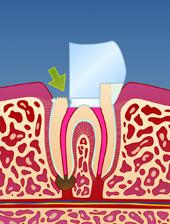

En rotfylt tann er ofte svekket på grunn av store fyllinger og lite gjenværende tannsubstans (fig. I). Som resultat vil en rotfylt tann være mer utsatt for å knekke enn en tann som ikke er rotfylt (fig. II-III). Dersom rotfyllingen blir utsatt for lekkasje over lengre tid, kan bakterier komme til og lage en ny infeksjon i den rotfylte tannen (fig. IV). Der er derfor viktig å kontakte tannlege snarest dersom deler av en rotfylt tann knekker av.

| figur I | | figur II | | figur III | | figur IV |